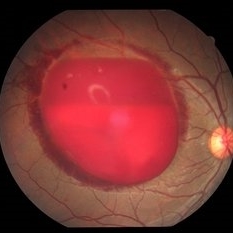

Sub-Hyaloid Hemorrhage

May 11 2020 by Gayathri Mohan

Color fundus photograph of a patient with a boat shaped sub hyaloid hemorrhage.

Photographer: Gayathri Mohan, Retina Foundation

Imaging device: Mirante, Nidek

Condition/keywords: subhyaloid hemorrhage, ultra-wide field imaging